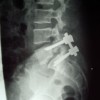

Espondilolistesis